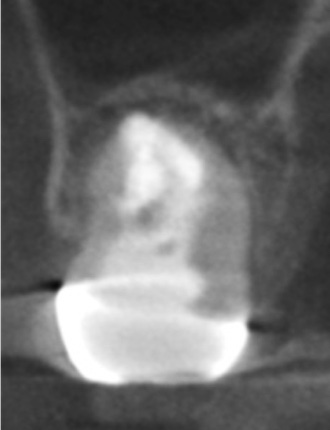

かぶせ物が不適であること(青矢印部)、近心根に根尖病巣があること(青枠部)、根充剤がかなり太いため(赤矢印部)歯質が薄くなっていることなど問題点がいくつかありましたが、他院で治療をしたばかりであり、また上記の条件から再治療には抜歯のリスクが非常に高いことから初診時は患者さんと相談し経過観察することになりました。